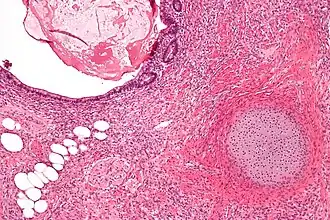

Micrografia de um teratoma com componentes gastrointestinais (direita superior) cartilagem (direita inferior) e tecido adiposo (esquerda inferior). Tingido com Hematoxilina-Eosina.

O cisto dermóide é um dos tumores mais comuns do ovário e um exemplo de teratoma. Macroscopicamente é um tumor cístico preenchido por cabelos e material sebáceo. A parede interna do cisto tem aspecto de pele, com epiderme, folículos pilosos, glândulas sebáceas e sudoríparas. Geralmente, em uma área da parede mais saliente na luz do cisto e chamada promontório, encontramos vários outros tipos de tecido, que tipicamente derivam dos três folhetos embrionários. Alguns cistos dermóides parecem um atlas de histologia normal pela variedade de aspectos. Porém, os tecidos estão topograficamente desorganizados e agrupados sem nenhuma 'lógica'. Em diversas áreas podemos reconhecer estruturas organóides, como a que lembra víscera oca, com musculatura lisa em duas camadas e portanto ate esboço de inervação autonômica. Vemos tecido nervoso central (ectoderme) com áreas de gliose e até diferenciação para córtex cerebelar. Há vários tipos de epitélio de revestimento: escamoso, cilíndrico ciliado, com ou sem células caliciformes, e do tipo intestinal (endoderme). Há ainda glândulas mucosas, serosas e sero-mucosas (também da endoderme) e tecidos de linhagem conjuntiva como músculo liso e osso (mesoderme). Em suma, qualquer tecido normal pode estar presente.